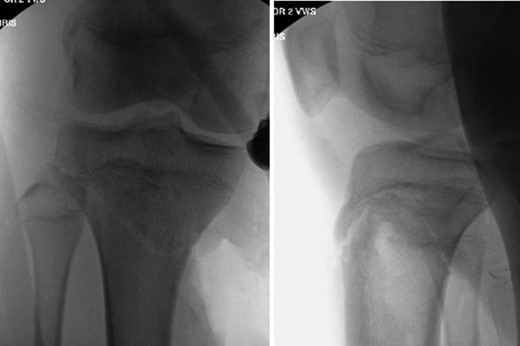

Patient is a 14-year-old male who slipped and fell while jumping off of a diving board and landed onto a flexed right knee. The patient was stable on presentation and neurovascularly intact with the knee locked in flexion. Skin was tenting anteriorly over the tibial tubercle and his compartments were swollen but compressible. A single plain film view (Fig. 1) was obtained prior to orthopaedic consultation. Closed reduction under sedation and splitting was attempted in the ED with partial but unsatisfactory improvement. Post-reduction radiographs (Fig. 2) demonstrated a tibial tubercle fracture with extension through the entire proximal tibial physis with metaphyseal involvement posteromedially. We classified this as a type IV tibial tubercle fracture, Salter–Harris II variant. In conjunction with patient and family we planned for urgent closed versus open reduction and application of knee-spanning external fixator. Immediately prior to surgery in the pre-operative holding area, the patient noted increasing right leg pain. In the operating room (OR), a marked increase in swelling with tense skin was observed. Due to rapidly progressive swelling and nature of the fracture, the decision was made to proceed with a 4-compartment fasciotomy of the right leg. The medial-sided fasciotomy (Fig. 3) revealed significant bulging of the superficial and deep compartments; however, the anterior and lateral compartments were less swollen. The fracture was unable to be closed reduced intraoperatively, therefore proximal extension of the medial fasciotomy wound was performed to open and reduce the fracture under direct visualization. Anatomic reduction was achieved and a knee-spanning external fixator was applied (Fig. 4). Approximately 72 hours later the patient was brought back to the OR for irrigation and debridement, lateral wound closure, and medial wound vacuum placement. Another 72 hours later, he returned to the OR for removal of the external fixator, ORIF, and split-thickness skin grafting of the medial fasciotomy site. An anterolateral approach was used with a 3.5 mm proximal tibial locking plate (Fig. 5). At most recent follow-up (Fig. 6), six months post-op, the patient is pain free, ambulating without assistive device, and has returned to all desired activities.

AP and lateral radiographs after attempted closed reduction which reveal type IV tibial tubercle fracture with posteromedial metaphyseal extension (Salter–Harris II variant).